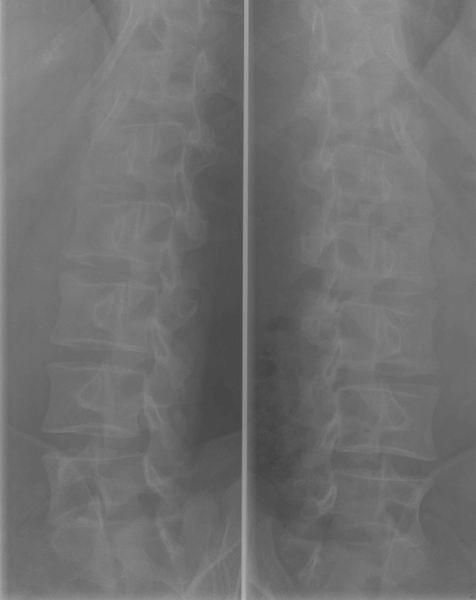

Dorsale wervelzuil